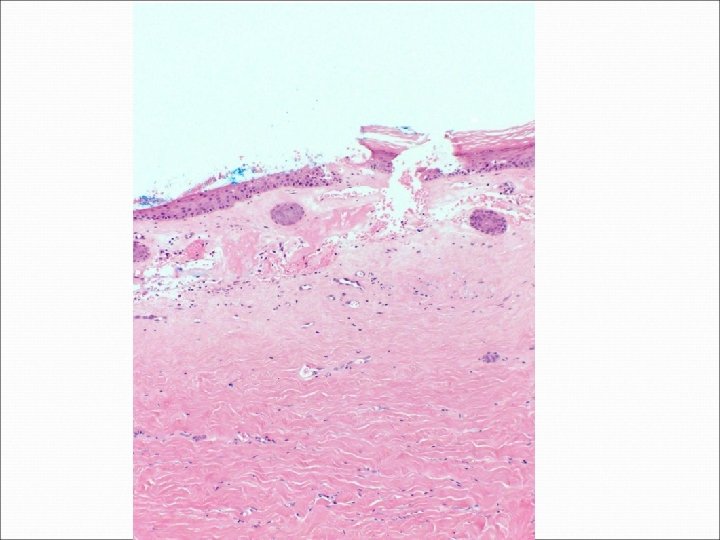

�Case number: 188 �Female aged 62. �? Multiple cysts posterior neck. �Specimen: Punch biopsy

�Case number: 188 �Female aged 62. �? Multiple cysts posterior neck. �Specimen: Punch biopsy �Macro: 3 x 3 x 4 mm punch biopsy.

Most popular diagnosis Malignant, probably metastatic lobular breast 9. 70